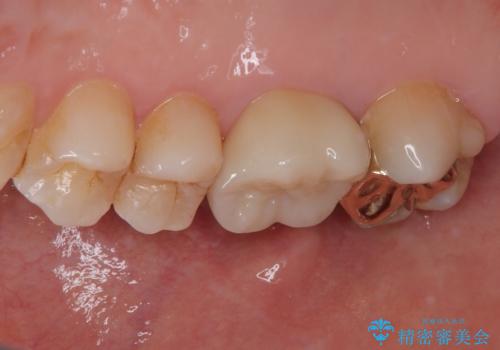

右上の6番目の歯はメタルインレーが大きかったためルジルコニアクラウン、右上の7番目の歯は一番奥で審美的な要素よりも機能面を重視してゴールドインレー修復による治療計画を立案しました。

見た目と機能面ともに満足していただきました。

矯正直後なので、リテーナーをあまり作り変えたくなかったのでリテーナーの制作回数が最小になるように治療計画を立案しました。